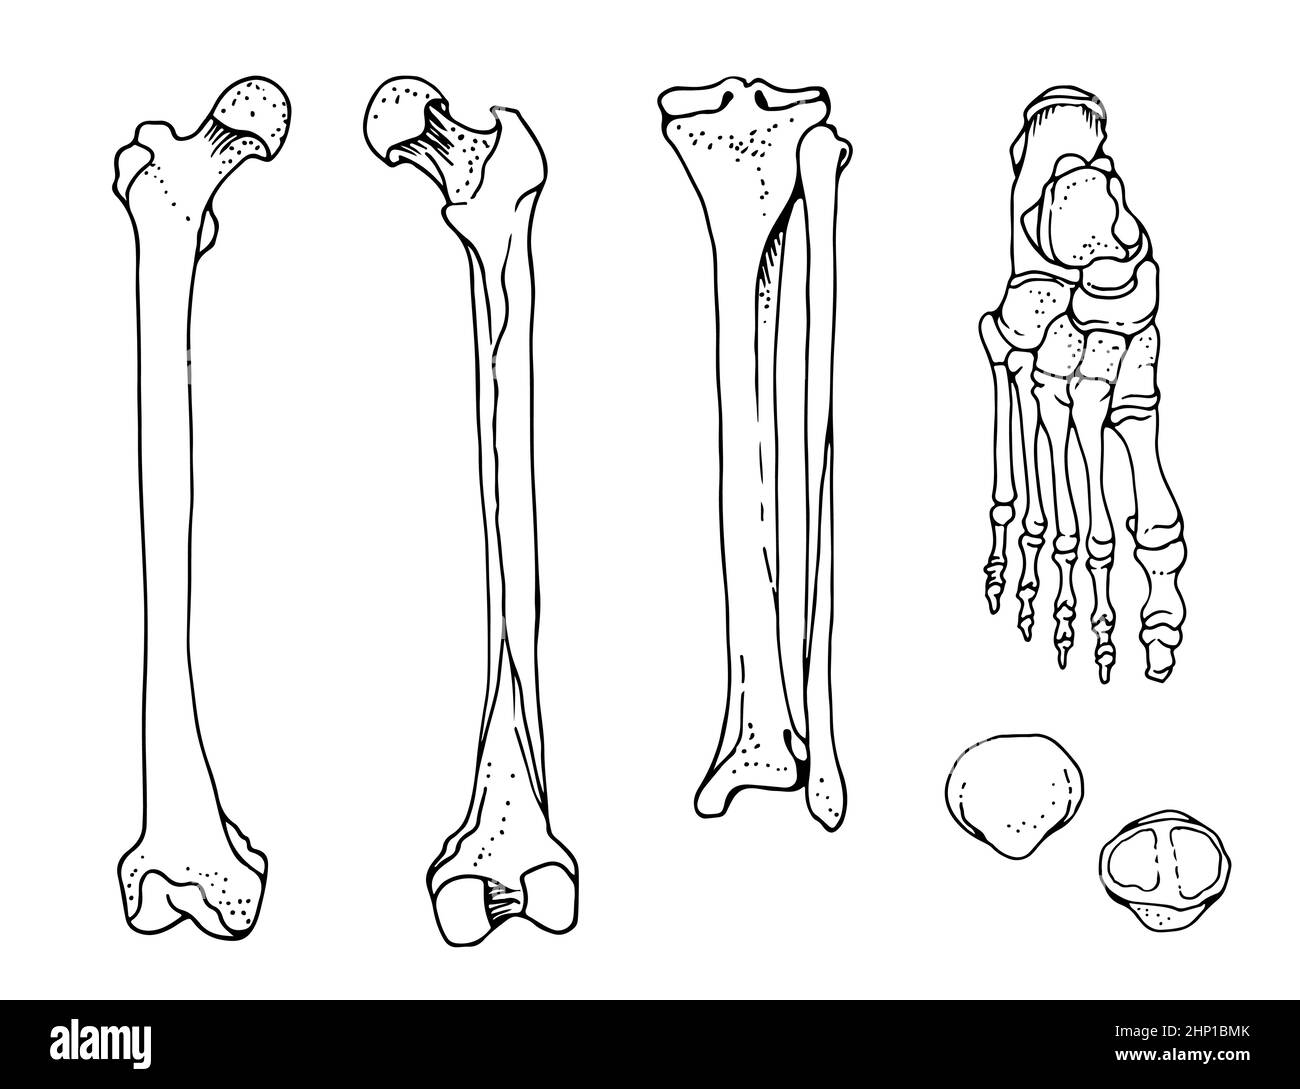

RF2HP1BMK–OS du pied humain, fémur, tibia et péroné, pied, rotule, illustration vectorielle dessinée à la main isolée sur fond blanc, ensemble anatomique orthopédique